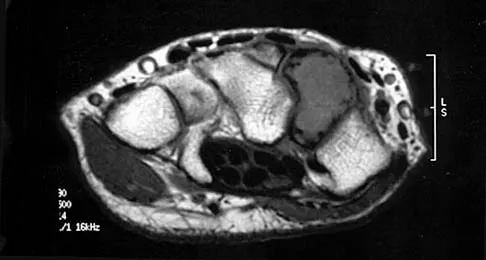

Figures 25a and 25b show the radiograph and MRI scan of a 7 1/2-year-old boy who has been limping for 1 year. His pain has worsened over the past 2 weeks, and his parents note swelling over the dorsum of the foot for the past 4 days. Examination reveals no fever, and laboratory studies show a WBC of 6,700/mm3, an erythrocyte sedimentation rate of 26 mm/h, and a normal C-reactive protein level. What is the most likely diagnosis?

Explanation